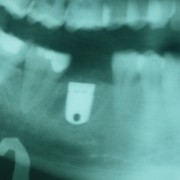

Immediate Molar Implant